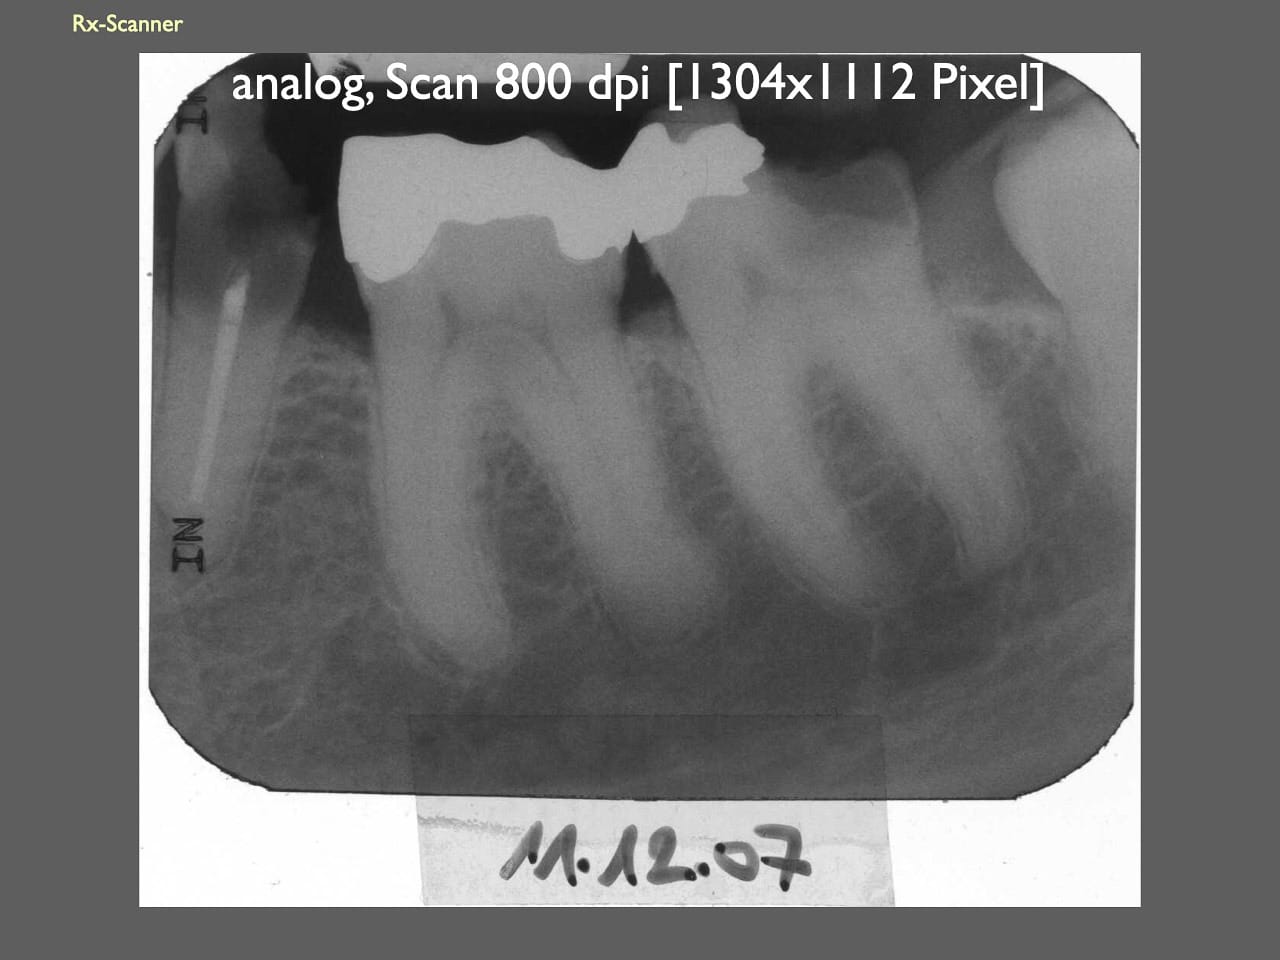

dental Scannen in der Zahnarztpraxis. Study Club vom 28.2.2010. Von peter portmann, Veröffentlicht am 28. Feb. 2010 — 3 min Lesezeit dokumentationfoto Auf dieser Seite Zahnarztpraxis-Trilogie zu Fotografie und Dokumentation Portrait Fotografie Scannen Scannen